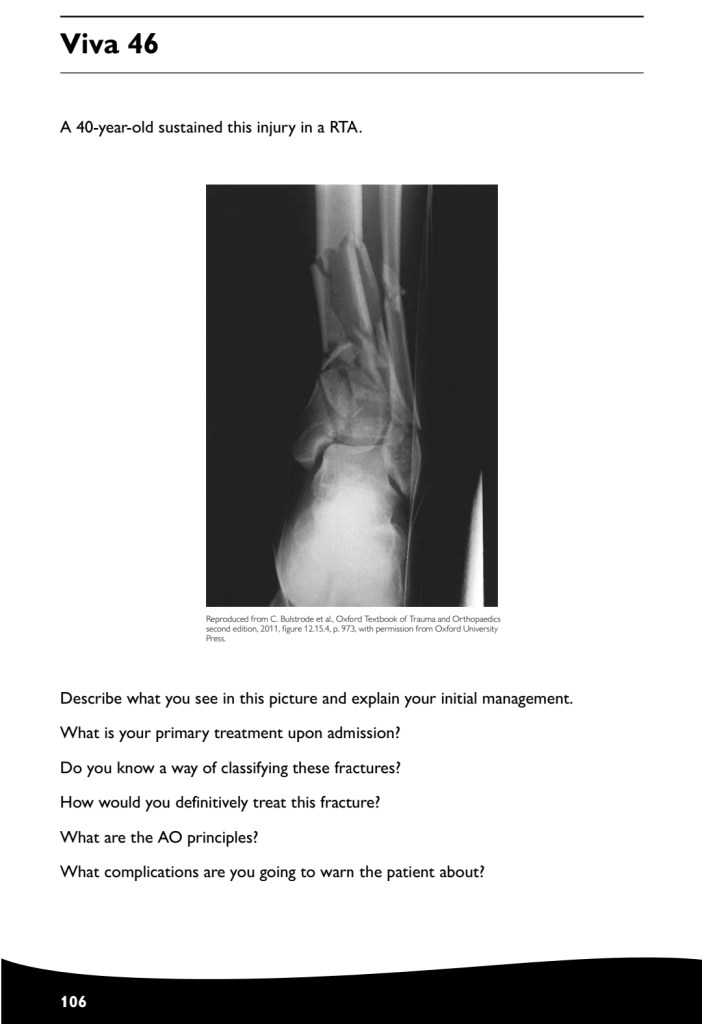

Revision how to answer your case